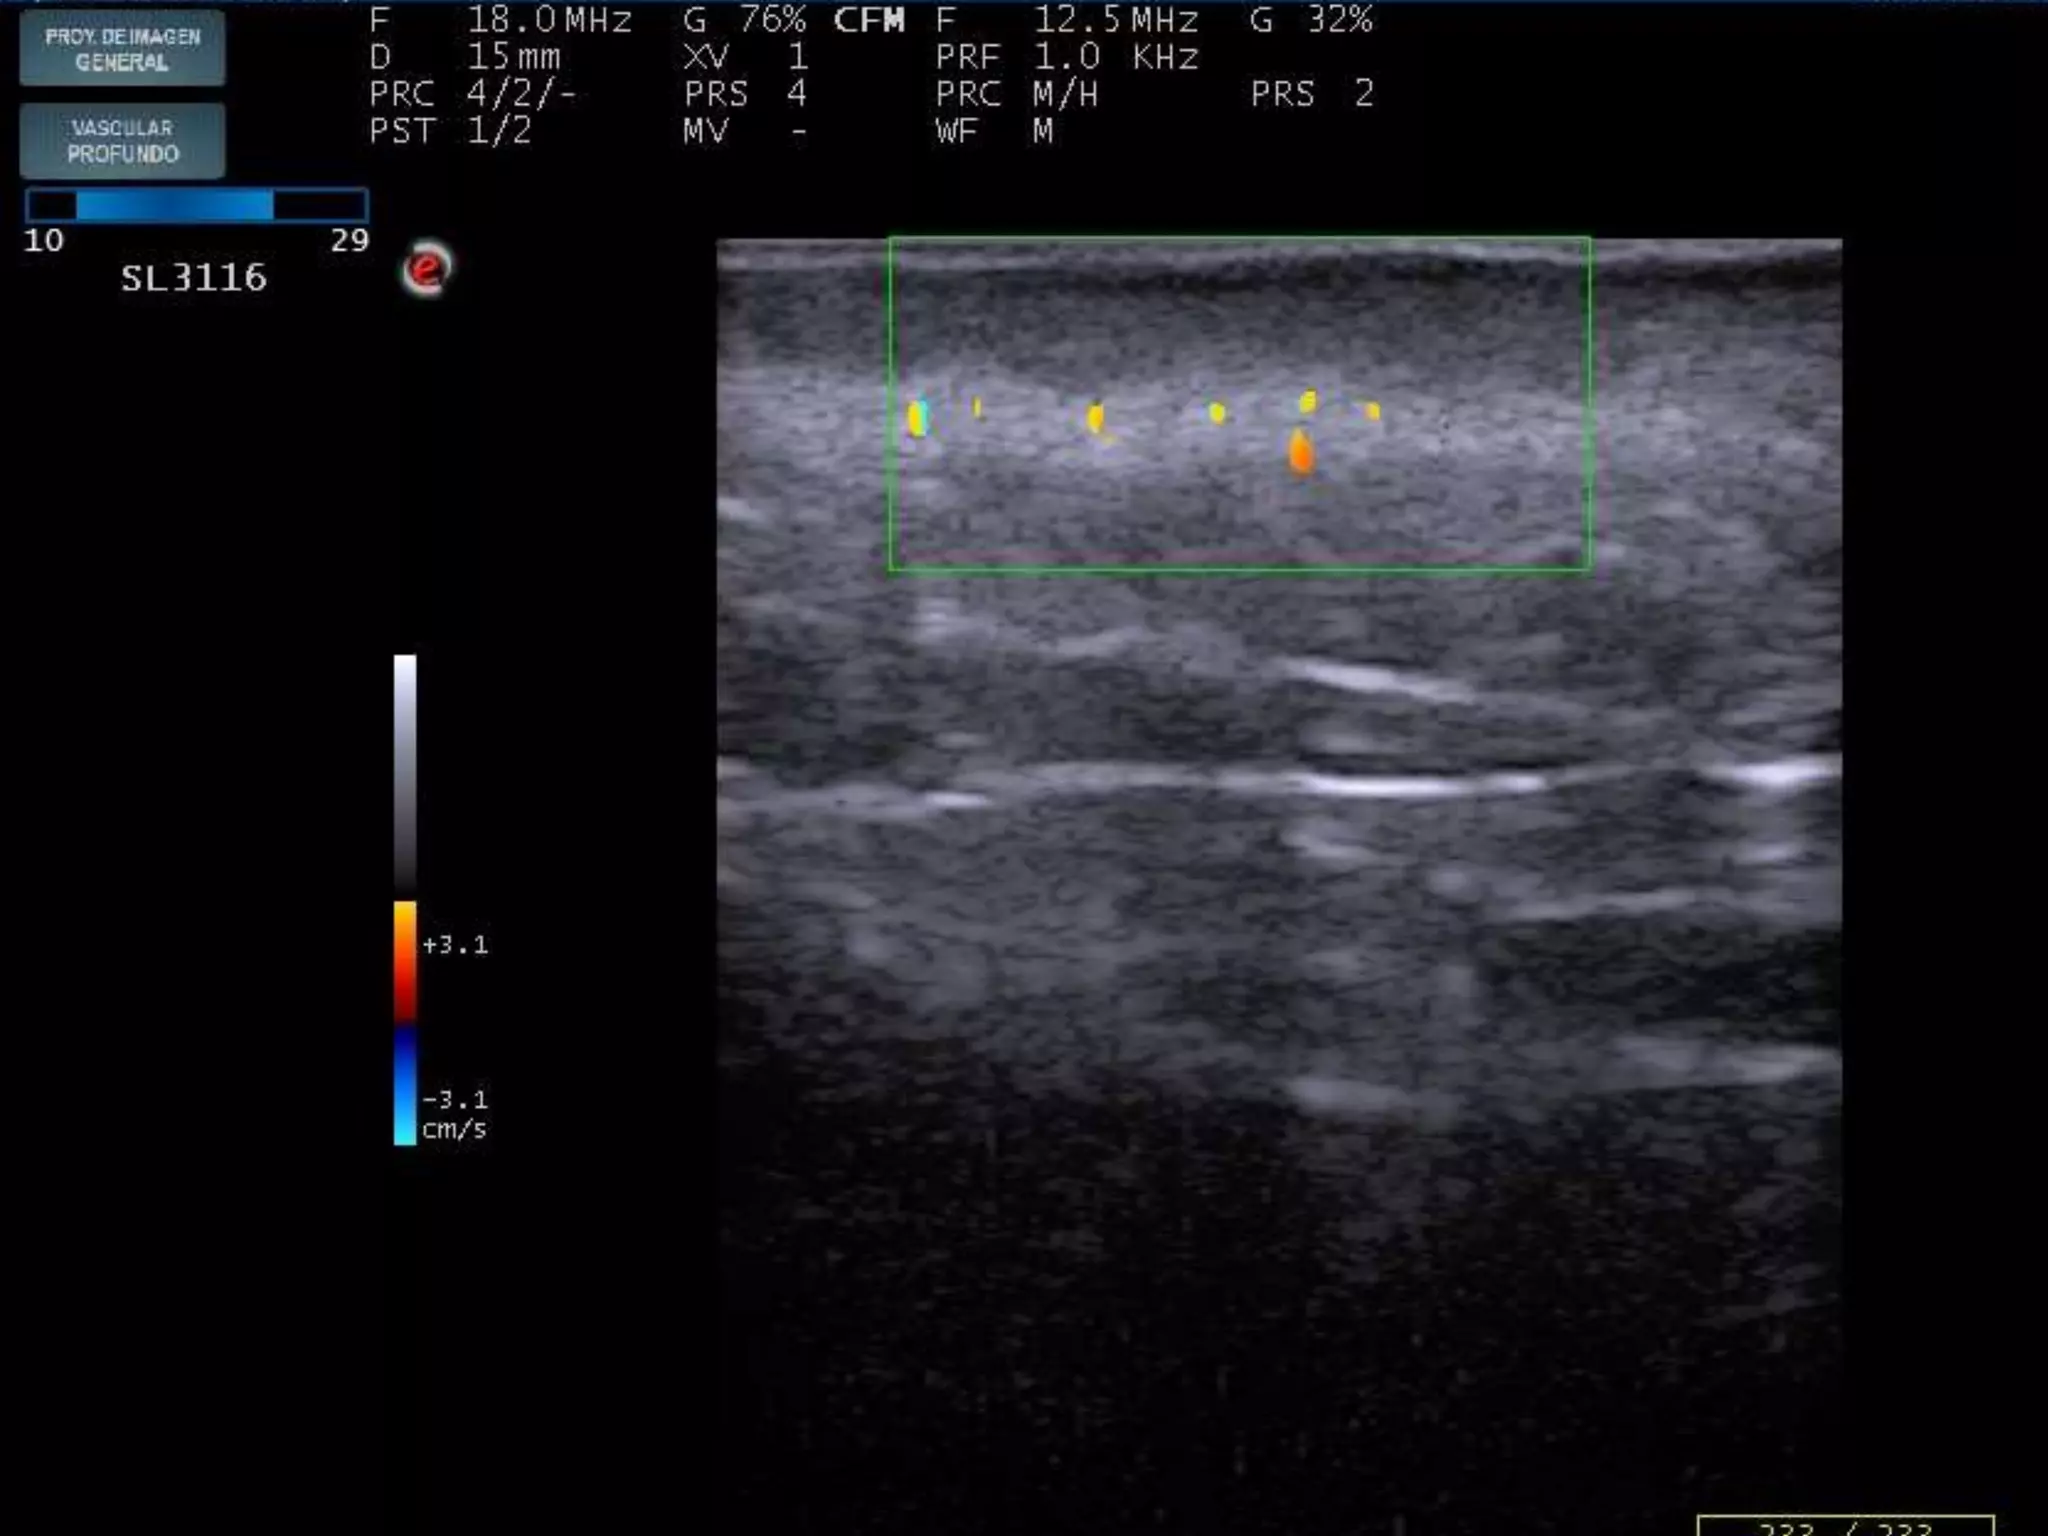

INFLAMADO

LOCALIZACION DE INFLAMACION

DERMIS

ACNE PAPULOPUSTULOSO

UNION DERMOEPIDERMICA

LIQUEN PLANO

REGLAS “FÁCILES”

PARA DETECTAR INFLAMACION

1)La estructura inflamada se suele hacer

Hipoecoica = edema+células

2)El flujo Doppler Suele estar aumentado=

Aumento de flujo sanguíneo

3) COMPARAR, COMPARAR, COMPARAR